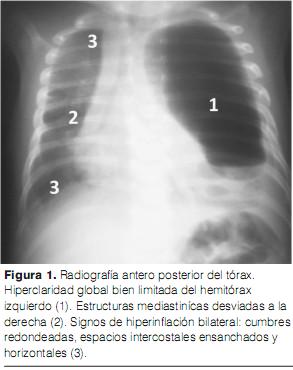

Ante este cuadro clínico, se realizan una radiografía de frente estándar (figura 1) y una TAC torácica (figuras 2, 3 y 4). La ecografía cardiaca y la ecografía abdominal son normales.

La radiografía estándar del tórax es un examen esencial en el diagnóstico del ELC. Los signos a favor son hiperclaridad con signos de expulsión contralateral. Hay también signos de hiperinflación como: aspecto redondeado de las cumbres, espacios intercostales horizontales, disminución o aplanamiento de la cúpula diafragmática homolateral.